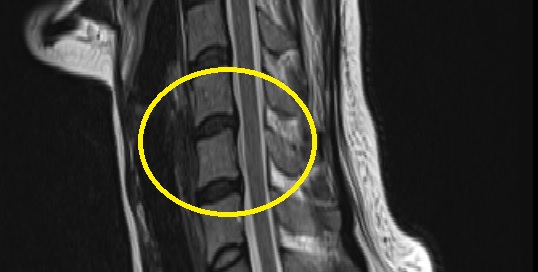

허리디스크에 의해 압박을 받고 있는 신경주위로 유착을 분리시키는 것을 말합니다.

꼬리뼈를 통해 유착된 부위를 확인하고 유착 방지제를 주입하여 증상을 완화시키는 것입니다.

수핵탈출증